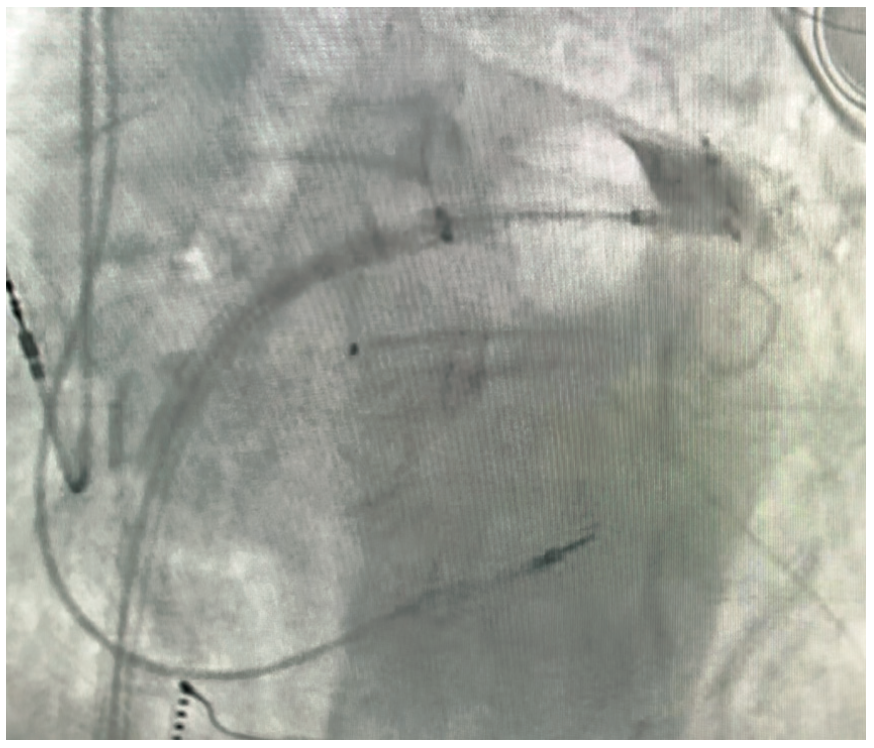

Pulmonary vein isolation (PVI) using cryoballoon (CB) ablation is an established therapy for treatment of patients with symptomatic paroxysmal and early persistent atrial fibrillation (AF).1,2 Complete PV occlusion with the CB ablation catheter is recommended prior to freezing to achieve successful PVI. CB ablation, as it was first described in 2005, required the use of an intravenous (IV) contrast injection through the central lumen of the CB catheter to verify complete PVI with the balloon catheter.3 To this day, most electrophysiology labs, including our lab at St. Anthony’s Hospital in Lakewood, Colorado, use IV contrast injection under fluoroscopy as the standard of care to confirm complete PVI prior to delivery of CB ablation therapy (Figure 1, Video 1).

Video 1. Fluoroscopic view of the CB ablation catheter advancing to PV ostium, followed by IV contrast injection and demonstrating complete PV occlusion.